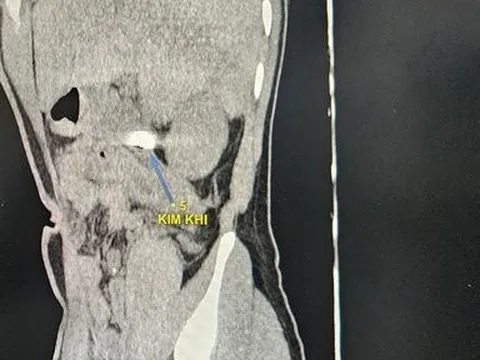

Bé trai vỡ khí quản, nguy kịch tính mạng do ngã vào kệ tivi

Ngày 4/4, bác sĩ tại Bệnh viện Nhi Trung ương cho biết, vừa tiếp nhận một bé trai 7 tuổi vào cấp cứu trong tình trạng nguy kịch.